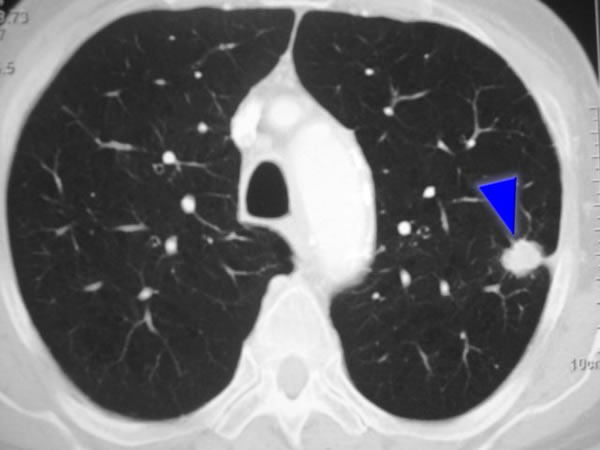

Importancia pronóstica de la determinación del calcio coronario en la TC de tórax para el rastreo de cáncer de pulmón

05 diciembre 2024

En las personas que se sometieron a una TC de tórax de baja dosis para la detección del cáncer de pulmón, la presencia de calcio en la arteria coronaria fue un predictor independiente de muerte por cualquier causa y eventos cardiovasculares, incluso después del ajuste por muerte no cardiovascular. Canadian Medical Association Journal, 2 de diciembre de 2024.